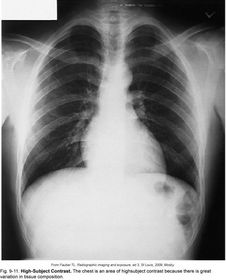

High-Subject Contrast - varying tissue types - varying shades of black -> gray -> white *CHEST*